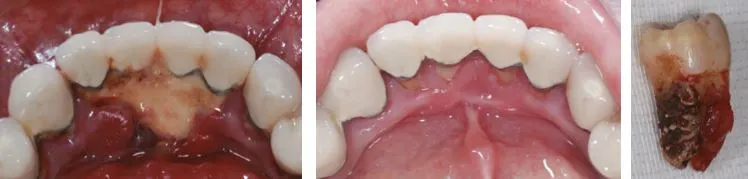

치주염.JPG

치은염.JPG

치주염(왼쪽) 과 치은염(오른쪽)

스케일링 전후.JPG 사진1, 2. 스케일링 전, 후

사진1, 2처럼 스케일링 전 후 호전되고 있는 부분을 볼 수 있으며 오른쪽 사진은 플라그와 치석이 방치되어 포도송이처럼 악화된 경우라고 할 수 있다.